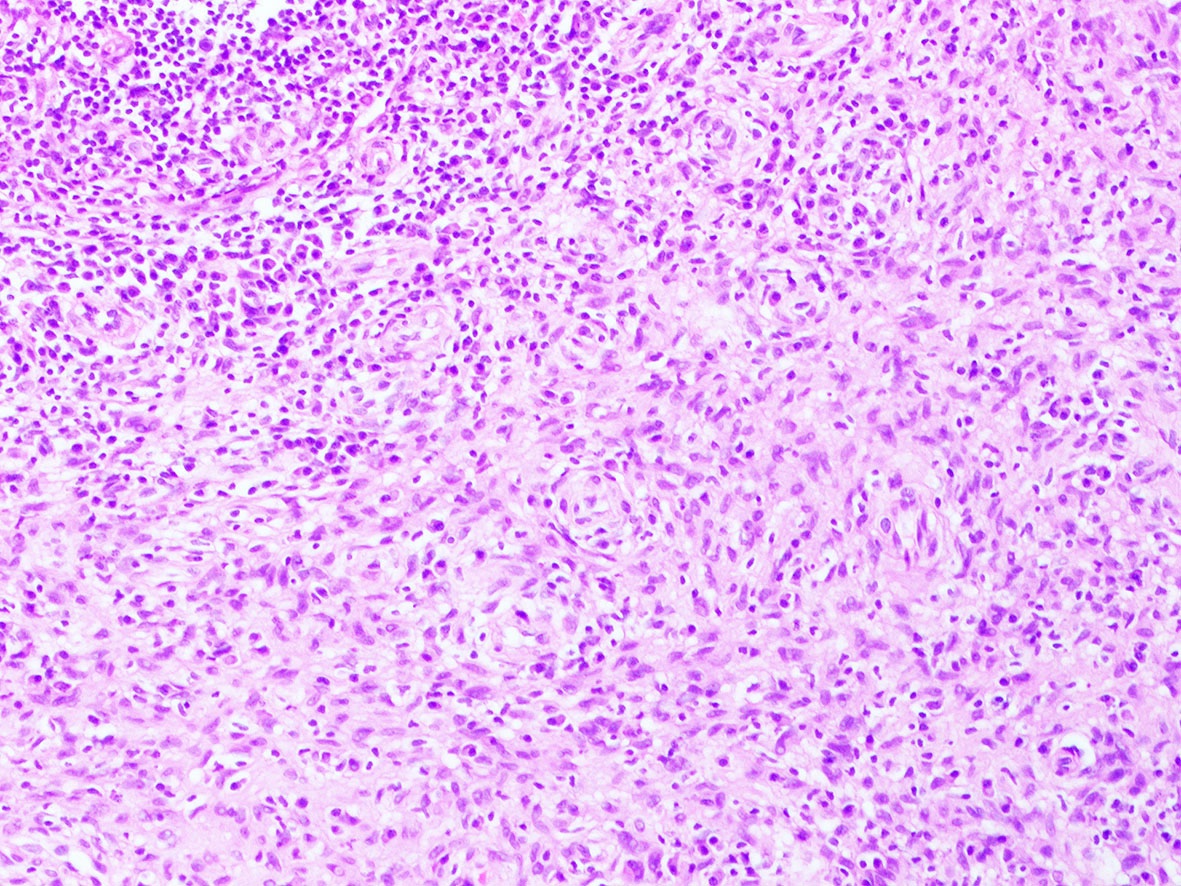

Microscopic (histologic) images

Contributed by A. Cristina Vargas, M.B.B.S., Ph.D., Patricia Guzman, M.D., Fiona Bonar, M.B.B.Ch., Alison Cheah, M.B.B.S. and Martin Jones, M.B.B.S.

Positive staining - disease

- ALK overexpression as a result of gene translocations / fusions:

- ALK+ anaplastic large cell lymphoma (ALCL) (Science 1994;263:1281, Semin Diagn Pathol 2020;37:57)